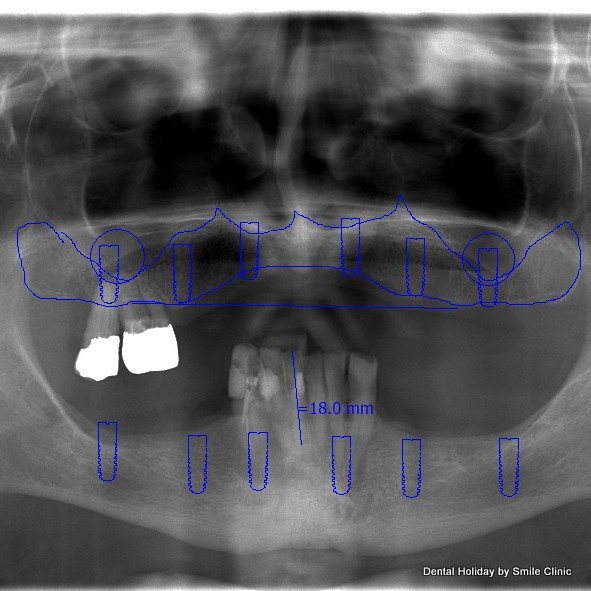

At the beginning of his first visit to Piešťany dental clinic, he had a consultation appointment with Dr Marek. The doctor suggested All on 6 dental implants treatment for him. In order to place the dental implants, bone graft on his upper jaw was needed. We made all necessary X rays and CT scans and started the treatment on the second day of his visit. The doctor took 2 of Alan’s remaining teeth out, did the bone graft and successfully put 6 dental implants in Alan’s upper jaw. The doctor put a healing abutment on each dental implant and temporary dental crowns were provided as well.

On the third day of Alan’s visit, we continued the treatment with his lower jaw. After the extraction of 6 teeth, Dr Marek put 6 dental implants in his lower jaw. The surgery took 4 hours in the dental chair and stage 1 of the All on 6 procedure for both jaws was completed. After a quick after-surgery check up on the next day Alan flew back to the UK.

On the third visit, we finished Alan’s dental treatment. We removed his temporary dental crowns and put 14 porcelain dental crowns on his upper jaw and 14 dental crowns on his lower jaw.